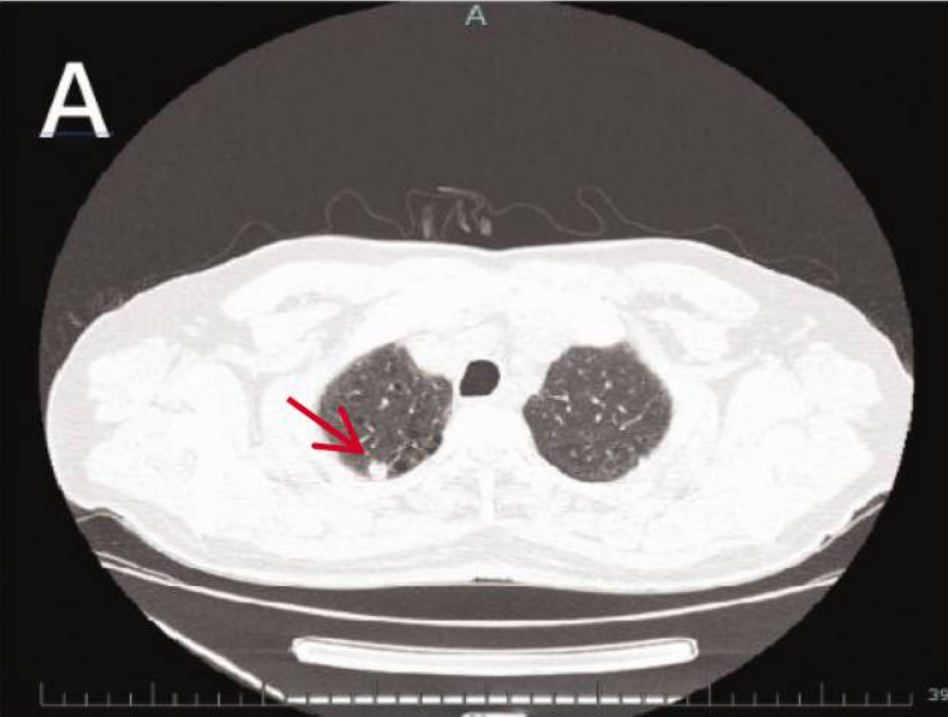

胸部CT:右肺上叶见一孤立性毛刺状结节,大小约9mm。

腹部MRI:肝VI-VII段交界区见一边界清晰的圆形病灶(大小46×36×32mm),动脉期呈高强化,门脉期及延迟期强化减退(“廓清征”),初步提示肝细胞癌

。

PET-CT:肝病灶、右肺门淋巴结及右肺上叶结节均表现为高代谢活性,符合转移性恶性肿瘤特征;胃肠道可见慢性炎症改变。

本病例中,患者因肝占位就诊,影像学提示肝、肺多发病灶。肝转移灶体积远大于原发肺病灶(46 mm vs. 9 mm),体现LCNEC极强的转移和增殖能力。此类快速增长在神经内分泌肿瘤中罕见,提示即使原发灶很小,也需高度警惕转移。